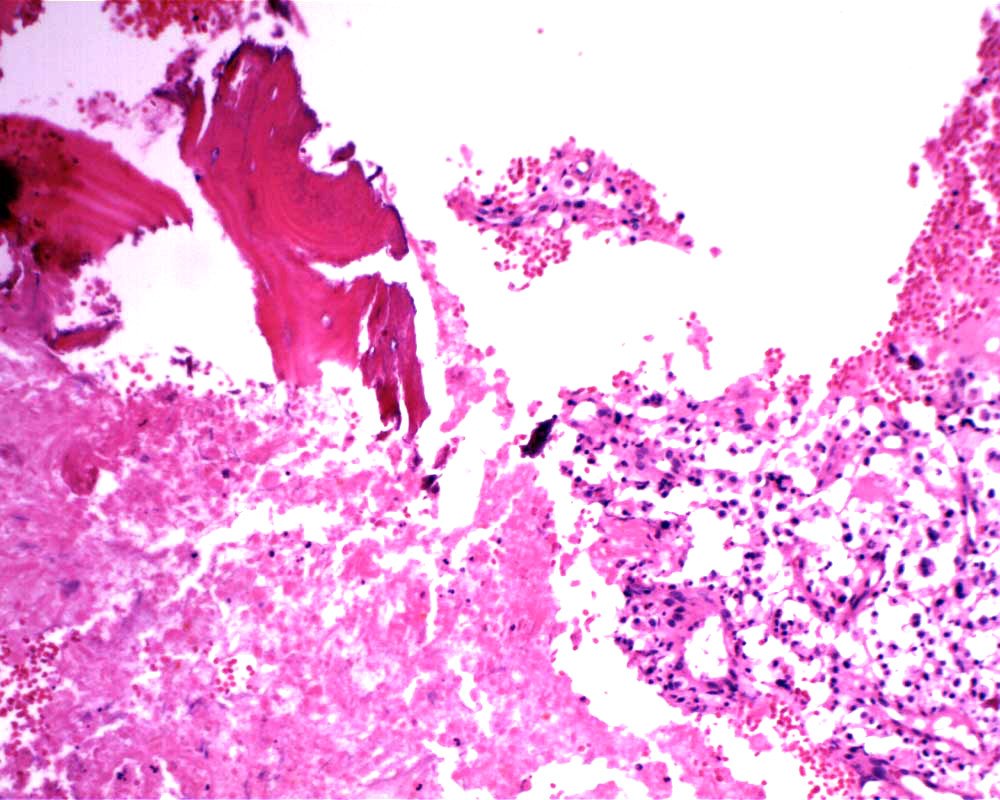

Case: FemurLesion

Final Diagnosis: